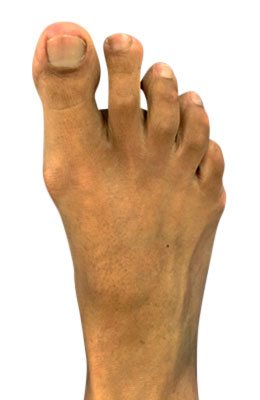

Lapidus Forever Bunionectomy™ and Hammertoe Correction with Tailor's Bunionectomy

Michael had neglected his painful foot for years because he was afraid of surgery and the pain. His condition deteriorated to much that he had a dislocated second toe, a bunion and tailor’s bunion deformity and severe hammertoes. Our foot and ankle surgeons performed extensive surgery on his foot correcting his bunion with a Lapidus Forever Bunionectomy™, relocation of his 2nd and 3rd metatarsal bone with metatarsal osteotomies and plantar plate repairs, hammertoe correction with our revolutionary Ossio implant and a tailor’s osteotomy bunionectomy. Michael was back on his foot 2 weeks after surgery and back in shoes in 8 weeks. He had no post-operative pain of significance and was so grateful that he invited us all to dinner at his restaurant (which was delicious)! The after image taken 12 weeks post-op.